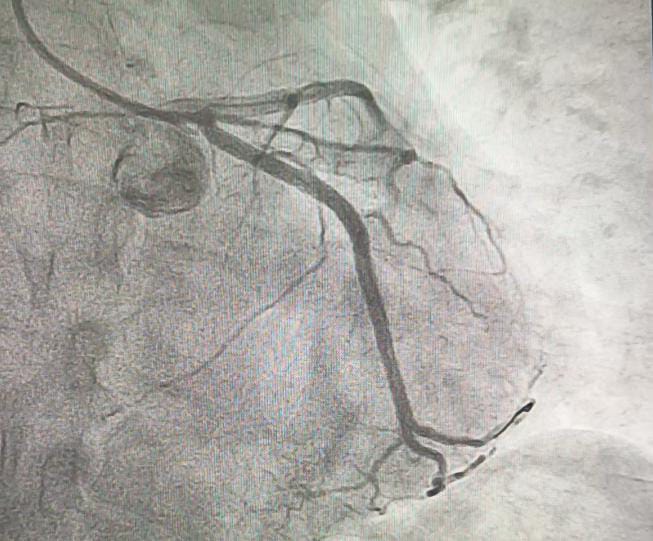

Coronary angiography revealed total occlusion of the proximal LCx and a sub totally occluded RCA with thrombus.

Both RCA and LCx were considered as the culprit lesion. We decided to addressed the lesion in RCA first, since the flow is still TIMI III. RCA was engaged with 6F JR guiding catheter. Run through wire was advanced distally to RCA. After pre dilatation with NC balloon 3.5 / 18 mm the thrombus disappeared. A 3.5 / 22 mm stent was implanted in RCA at 18 atm. Post dilatation with stent balloon at maximum pressure 20 atm. Final angiogram showed TIMI 3 flow. Then we intervene the LCx. We used BL guiding catheter to engage the LCx. Run through NS floppy wire was advanced to distal LCx. Coronary angiogram showed good contrast flow to distal LCx. Pre dilatation at proximal LCx with NC balloon 3.5 / 18 mm at 18 atm. DES was implanted at LCx at 20 atm. We did post dilatation at LCx with NC balloon up to 24 atm. Final angiogram showed TIMI III flow.

ECG finding in double culprit STEMI may be more diffuse than in single vessel STEMI. The challenge lies in identifying both culprit lesions during acute phase STEMI. In our case the lesions are more obvious. The lesion in RCA was addressed first because the distal flow was still good and we did not want any abrupt closure of the vessel since there were a large amount of thrombus in the lesion.